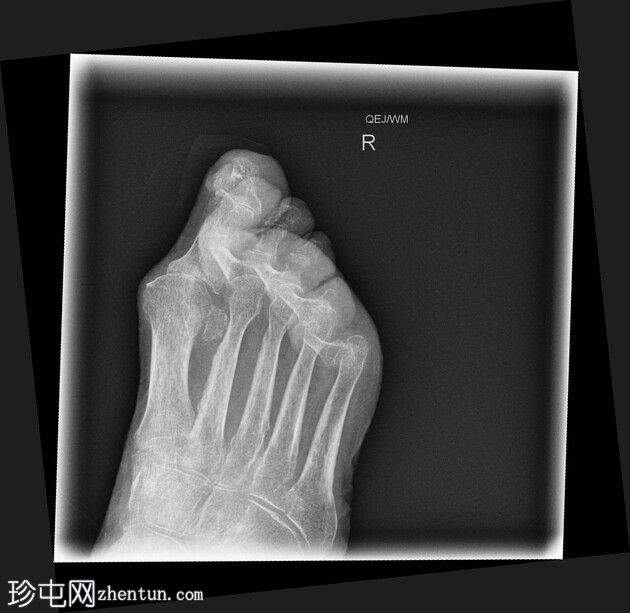

正位

第二至第五趾跖趾关节明显过伸,近端趾间关节屈曲,符合爪状趾畸形。部分远端趾间关节屈曲程度不及其他关节。